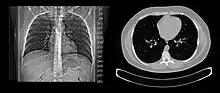

Lungs

A CT scan can be used for detecting both acute and chronic changes in the lung parenchyma, the tissue of the lungs.[41] It is particularly relevant here because normal two-dimensional X-rays do not show such defects. A variety of techniques are used, depending on the suspected abnormality. For evaluation of chronic interstitial processes such as emphysema, and fibrosis,[42] thin sections with high spatial frequency reconstructions are used; often scans are performed both on inspiration and expiration. This special technique is called high resolution CT that produces a sampling of the lung, and not continuous images.[43]

Bronchial wall thickening can be seen on lung CTs and generally (but not always) implies inflammation of the bronchi.[44]